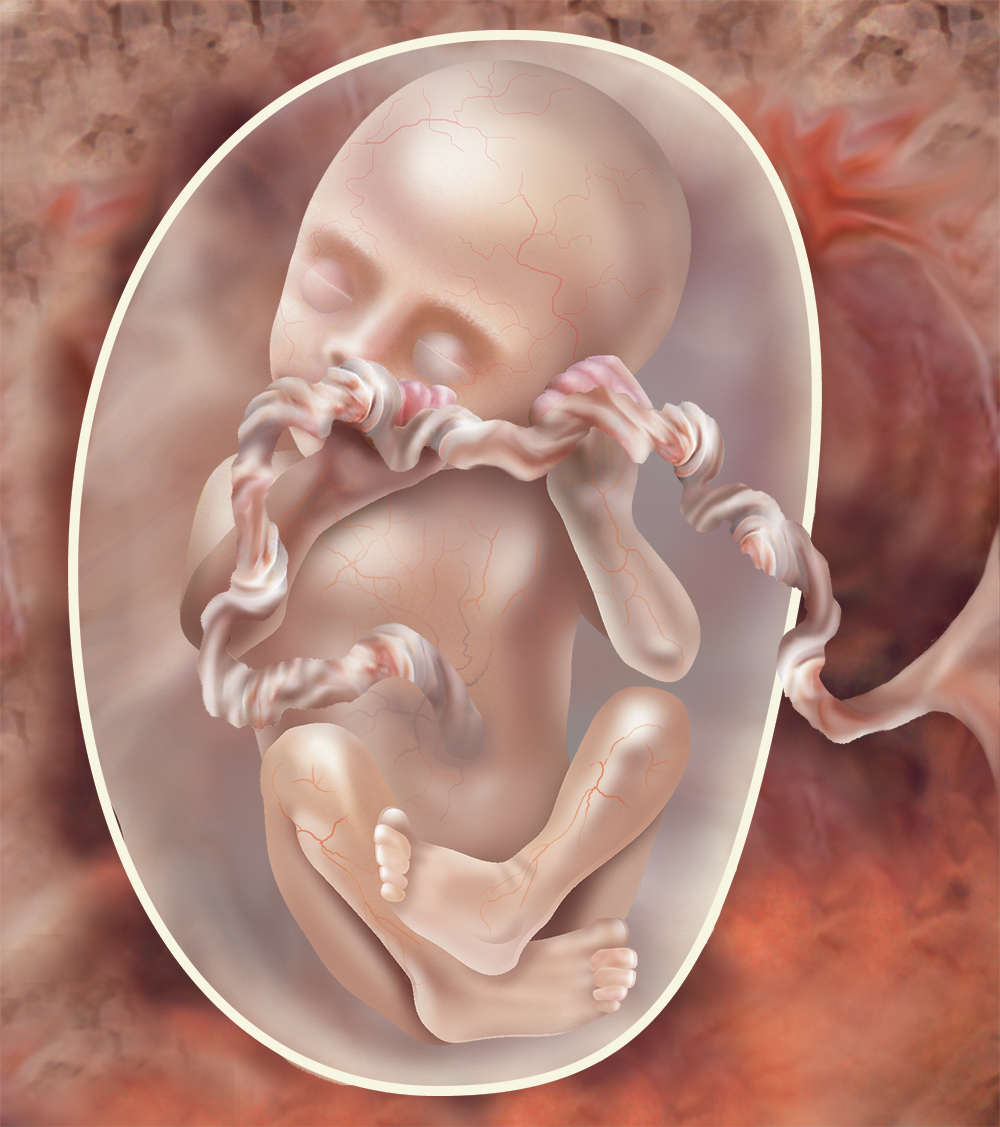

Этапы развития эмбриона человека: 14 недель